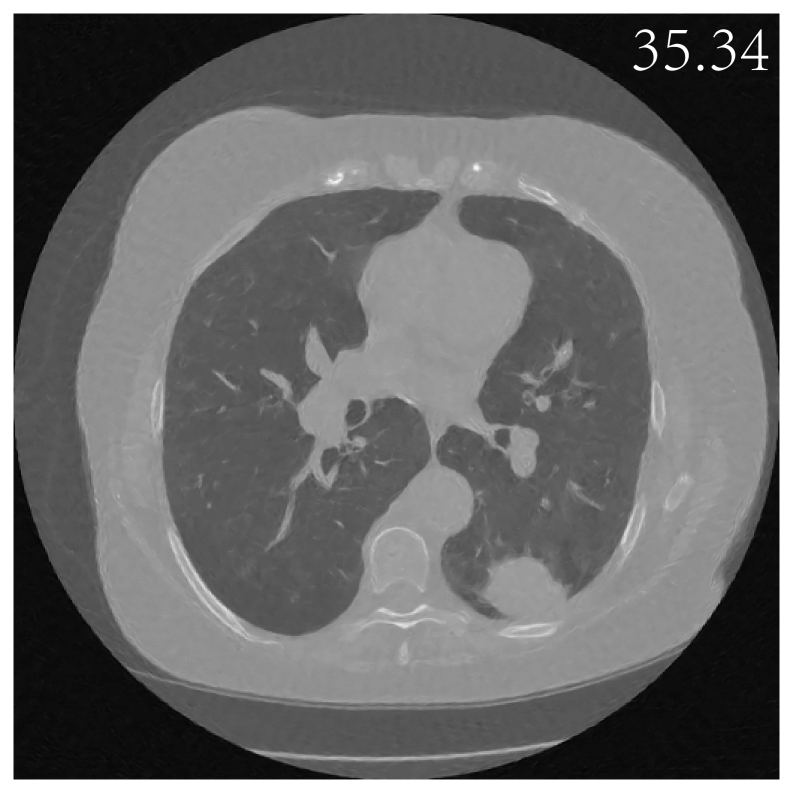

We first evaluate the performance of SkEI using a single sample from the resized sparse-view CT 100 dataset and then further compare this method with DIP and EI. For the vanilla EI method, we use the architecture suggested in chen2021equivariant to achieve the best performance and build the DIP using the same residual U-Net used in EI. For the sketched EI, we choose the subsampling sketch as our SS, which splits the measurement operator into NN minibatches, AS1,AS2ASNA_{S_{1}},A_{S_{2}}...A_{S_{N}} from interleaved angles. In each iteration, we randomly select one of the minibatch and perform the update. We test on the choices N=2,5,10,20N=2,5,10,20 respectively here. As shown in Figure 2, the baseline DIP frameworks deliver only modest reconstruction fidelity in our study, while the incorporation of the EI regularizer improves reconstruction precision. In particular, the sketch-guided EI model with N=10N=10 achieves the highest reconstruction quality of all the evaluated methods. To further study the impacts of the sketching operation, we performed ablation experiments with four different sketch sizes as reported in Figure 3 and Figure 4(a). We can observe that the results for Sketched EI are slightly better than full EI (vanilla EI), for the number of minibatch splits chosen to be 2, 5, 10, or 20 (corresponds to 50%, 20%, 10% and 5% of origin, respectively), and reach the best at splits 10. The result would deteriorate if we choose to sketch over aggressively (20 splits in this setting), indicating a phase transition.

Figure 3: CT Images (with corresponding PSNR) reconstructed by Sketched EI, with different sketch sizes. EI-full uses 100 CT scans, while 50%, 20%, 10% and 5% means only 50%, 20%, 10% and 5% of 100 CT scans used per iteration. (*) denotes the baseline.

Figure 4(b) illustrates that all methods achieve a significant decrease in mean square error (MSE) within the first 2000 seconds of training. The Sketched-EI exceeds the full EI (vanilla EI) in the convergence rate, achieving a faster decline in the MSE. Furthermore, among the sketched schemes employing minibatch splits of 2, 5, 10, and 20, the split-10 scheme demonstrates the most pronounced and rapid convergence.